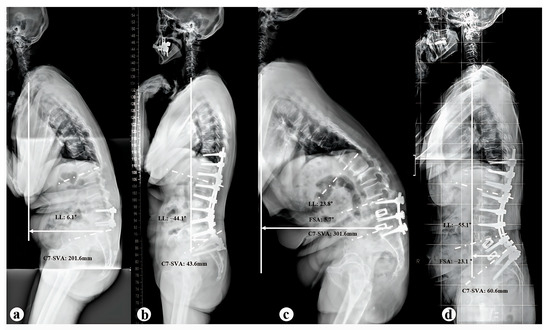

Indications for Additional Pedicle Subtraction Osteotomy in Iatrogenic Flatback After Short-Segment Fusion Surgery

Background and Objectives: This study aimed to identify radiographic predictors and optimal cut-off values for determining the need for additional pedicle subtraction osteotomy (PSO) in patients with iatrogenic flatback syndrome following short-segment (≤3 levels) fusion surgery. Materials and Methods: From 2011 to 2022, a total of 49 patients who underwent deformity correction for iatrogenic flatback following short-segment fusion at a single institution were included. We divided all patients into group A (n = 33, only anterior column realignment, ACR) and group B (n = 16, ACR combined with PSO). Among group A patients, we further divided them into two subgroups: The Excessive group, who developed excessive anterior disc height distraction (EADH) during surgery, and the Non-excessive group, who did not. The Receiver Operating Characteristic (ROC) curve was used to determine the cut-off values for spinopelvic parameters associated with the decision to perform additional PSO. Results: Group A had a significantly lower number of previously fused segments compared to Group B (p < 0.001). Preoperative C7 sagittal vertical axis (C7SVA, p = 0.026) and its correction (p = 0.003) in group B were greater than those in group A. Group B showed a significantly more kyphotic preoperative fused segment angle (FSA) compared to Group A (p = 0.001). Postoperatively, EADH occurred in 7 patients (21.2%) in Group A, while no cases were observed in Group B. Subgroup analysis revealed that the dynamic segment angle (DA) was significantly lower in the Excessive group compared to the Non-excessive group (p < 0.001). The optimal cut-off values of preoperative radiographic parameters for selecting PSO were: C7-SVA > 242.8 mm, FSA > −3.2°, and DA < 4.3°. Conclusions: ACR alone and ACR combined with PSO showed satisfactory outcomes in patients with iatrogenic flat back. For selected patients with preoperative C7SVA > 242.8 mm, FSA > −3.2°, or DA < 4.3°, additional PSO may be reasonable to help optimize sagittal alignment. Full article

Show Figures

Figure 1